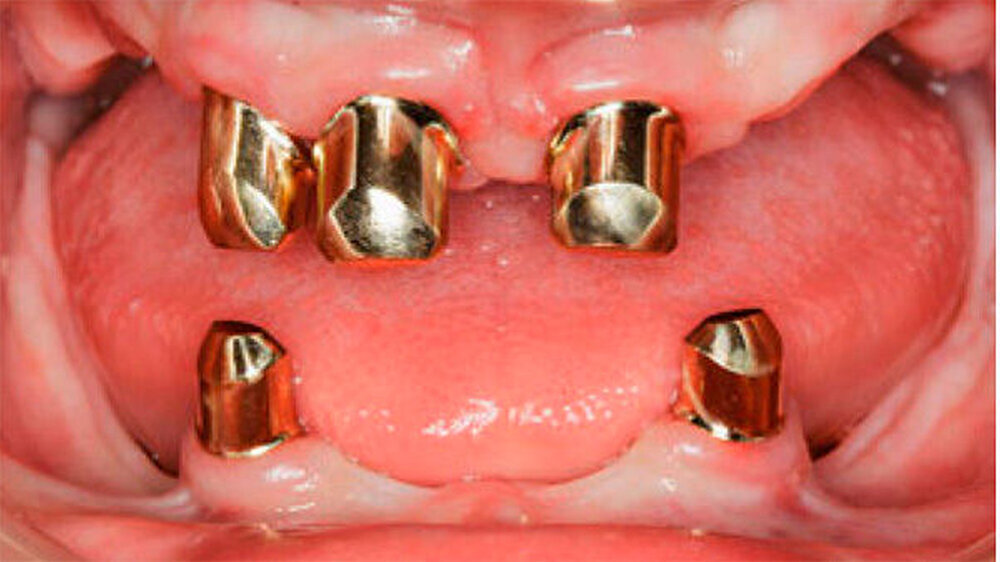

Nach Einprobe der Aufstellung der Prothesenzähne in Wachs wurden die Primärteile aus Gold und deren Galvano-Sekundärteile hergestellt. Letztere wurden in die fertige Prothese eingeklebt (Abb. 12 und 13). Auf eine gegossene Gerüstverstärkung wurde aufgrund des ausreichenden Platzangebots und der relativ geringen Kaufkräfte bei dieser, als Übergangsprothese geplanten Arbeit, aus Kostengründen verzichtet. Zur Erhöhung der Bruchzähigkeit erfolgte die Prothesenherstellung mit dem IvoBase® System (IvoBase® Injector, IvoBase® High Impact). Eine zusätzliche Glasfaserverstärkung zur Frakturprophylaxe wurde in den Prothesenkunststoff eingearbeitet.

Aufgrund des anatomisch sehr ungünstigen Prothesenlagers war der Erhalt der Restbezahnung im Oberkiefer anzustreben. Nach Kariesexkavation und Wurzelkanalbehandlung konnten beide Zähne mit einer Wurzelstiftkappe versorgt und die alten Prothesen entsprechend umgebaut werden. Im Anschluss an die Meisterabformungen und an die Ausrichtung der Wachswälle wurden die Modelle schädelbezogen einartikuliert, und die Prothesenzähne nach ästhetischen und funktionellen Richtlinien aufgestellt. Eine bilateral balancierte Okklusionsbeziehung konnte umgesetzt werden. Im Oberkiefer wurde eine gerüstverstärkte Totalprothese hergestellt, die auf den beiden Wurzelstiftkappen 16 und 26 verankert war. Im Unterkiefer konnte die Patientin mit einer Totalprothese versorgt werden (Abb. 21 bis 23).